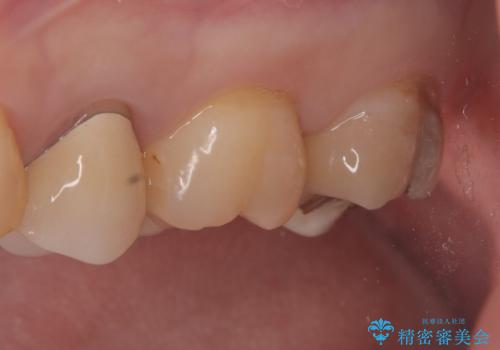

金属のインレーの下と、歯と歯の間も虫歯だったため、つなげた形でセラミックインレーにて修復を行なっています。

e-max プレスインレーを用いることで、適合の良い治療ができます。